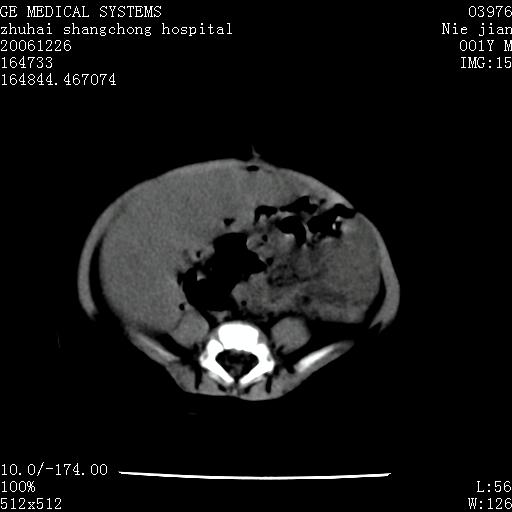

3个月婴儿腹胀来看。

【影像特征】

1、肝明显增大,肝弥漫性低密度灶。

2、肾上腺区见类圆形肿块,其内密度不均,见片状偏高密度。

【诊断】

1、肝弥漫性病变,考虑急性肝炎致广泛脂肪浸润可能性大。

2、肾上腺区占位,假性肿瘤?肾上腺血肿(感染所致)?

1、关键着眼点:肝脏弥漫性病变内有没有走形的血管,仔细看部分低密度内有血管影(要有增强扫描作为证据就好了),说明并非肿瘤样病变,而是脂肪浸润。即可能不是转移瘤或原发肿瘤,低密度的形态上看,是片状,也不像肿瘤。

3、肝炎的结局是肝硬化,而恰恰一年后复查,已有肝硬化表现。肿瘤一般那会消失,那叫奇迹。

4、肾上腺出血也可见于败血症及感染,通常包块在数周内消失,ct表现包块内有偏高密度,可能是亚急性血肿的表现。假性肿瘤即腹部肠管积液、扩张血管及邻近结构的伪像。自然会消失。